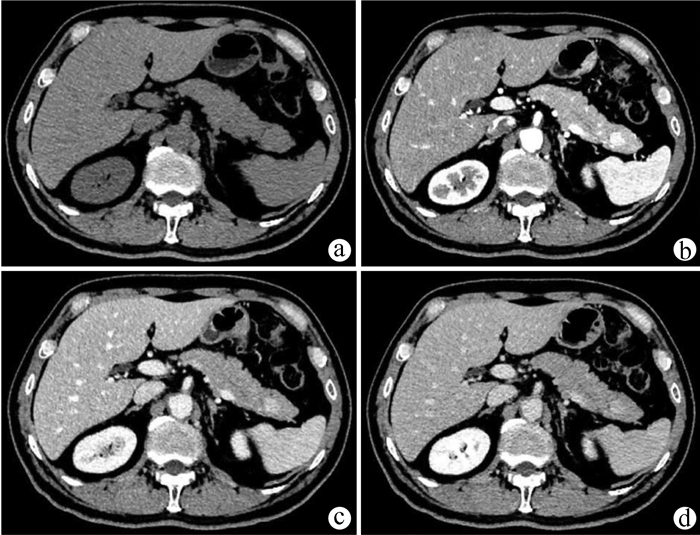

肝脏遗传性出血性毛细血管扩张症1例报告

王婷婷, 马亮, 陈建平

2022, 38(2): 423-425. DOI: 10.3969/j.issn.1001-5256.2022.02.032

摘要(1117) HTML (367) PDF (2696KB)(56)

摘要: